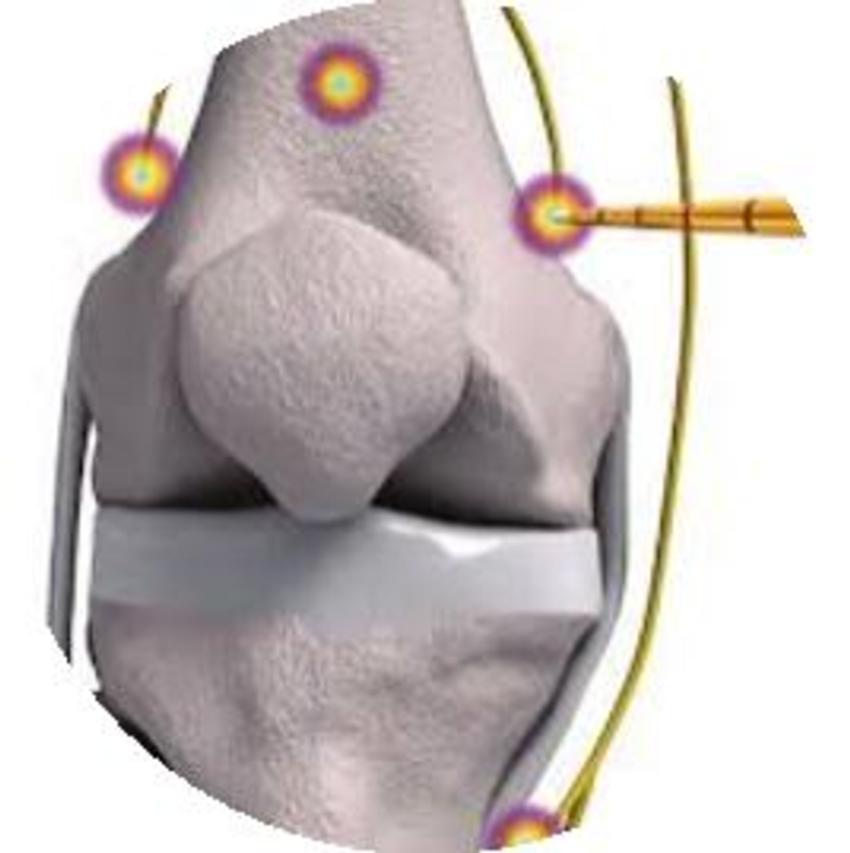

Figure 7. Genicular neurotomy targets.

High-res (TIF) version